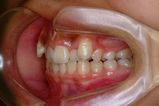

健康な小臼歯を抜いていません

矯正前                 矯正後

治療前 の 左 です 動く矢印治療後 の 左 です

治療前 の 右 です 動く矢印治療後 の 右 です